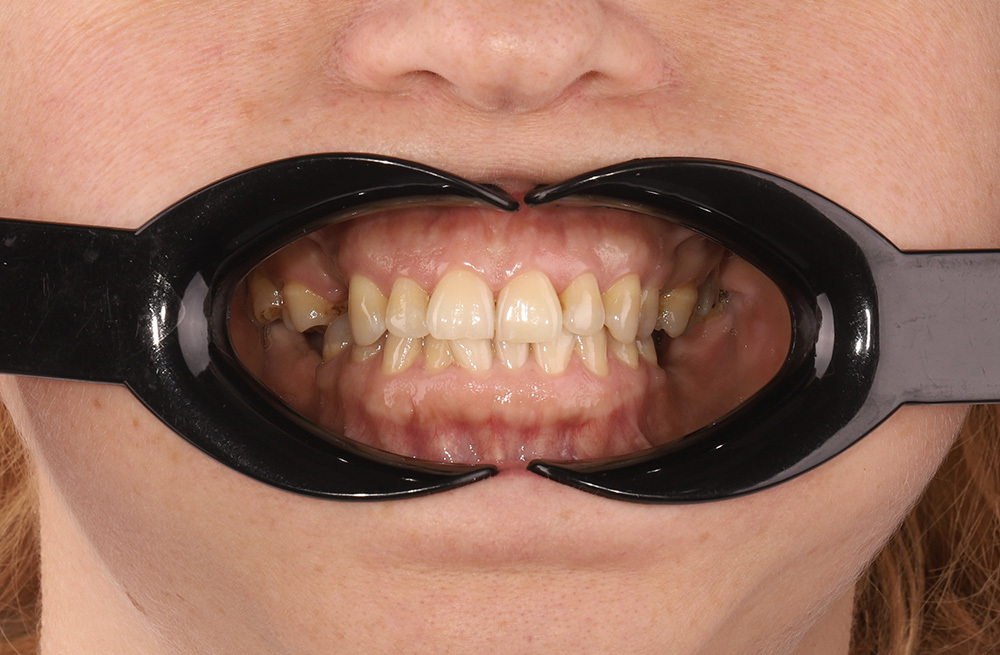

Комплексное ортодонтическое лечение у девушки с множественными нарушениями прикуса на фоне врождённой адентии боковых резцов